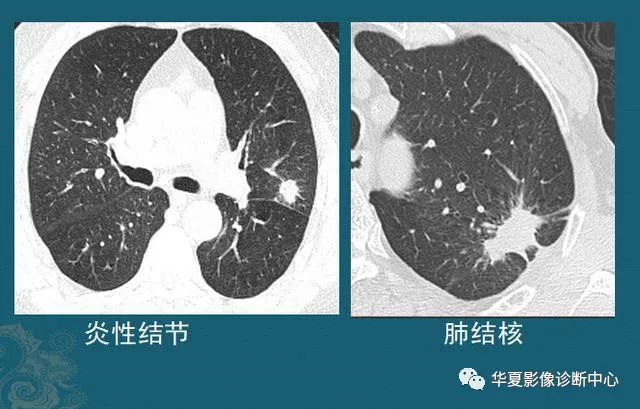

下图左边是一个炎症性结节,右图是结核球,都是形态不规则,边缘有毛刺,伴有胸膜牵拉:

图4

这种结节有时单纯从CT片的形态分析,跟肺癌鉴别困难,需要抗炎治疗后复查,或者增强CT看结节的强化特点,炎症结节常常明显均匀强化,结核球一般不强化或者环形包膜样强化(肺结核会破坏内部组织包括血管,引起广泛坏死),肺癌多为轻中度不均匀强化(肿瘤血管少而乱)。

还有些无法确诊的,需要多学科会诊,借助正电子发射计算机断层显像(PET-CT)或者穿刺,或者手术后病理等手段。